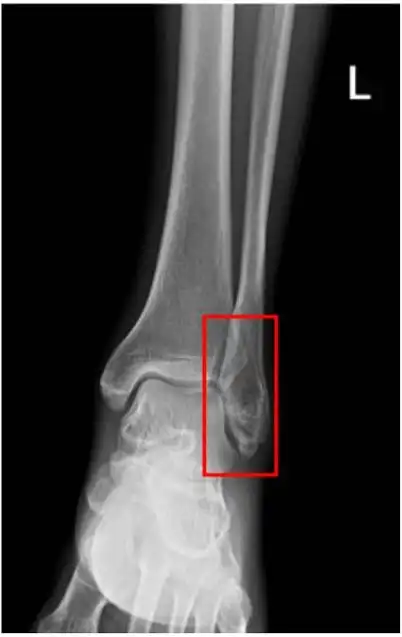

踝关节见横行骨折线又或者是这样的,急诊医生开的申请单是踝关节正侧